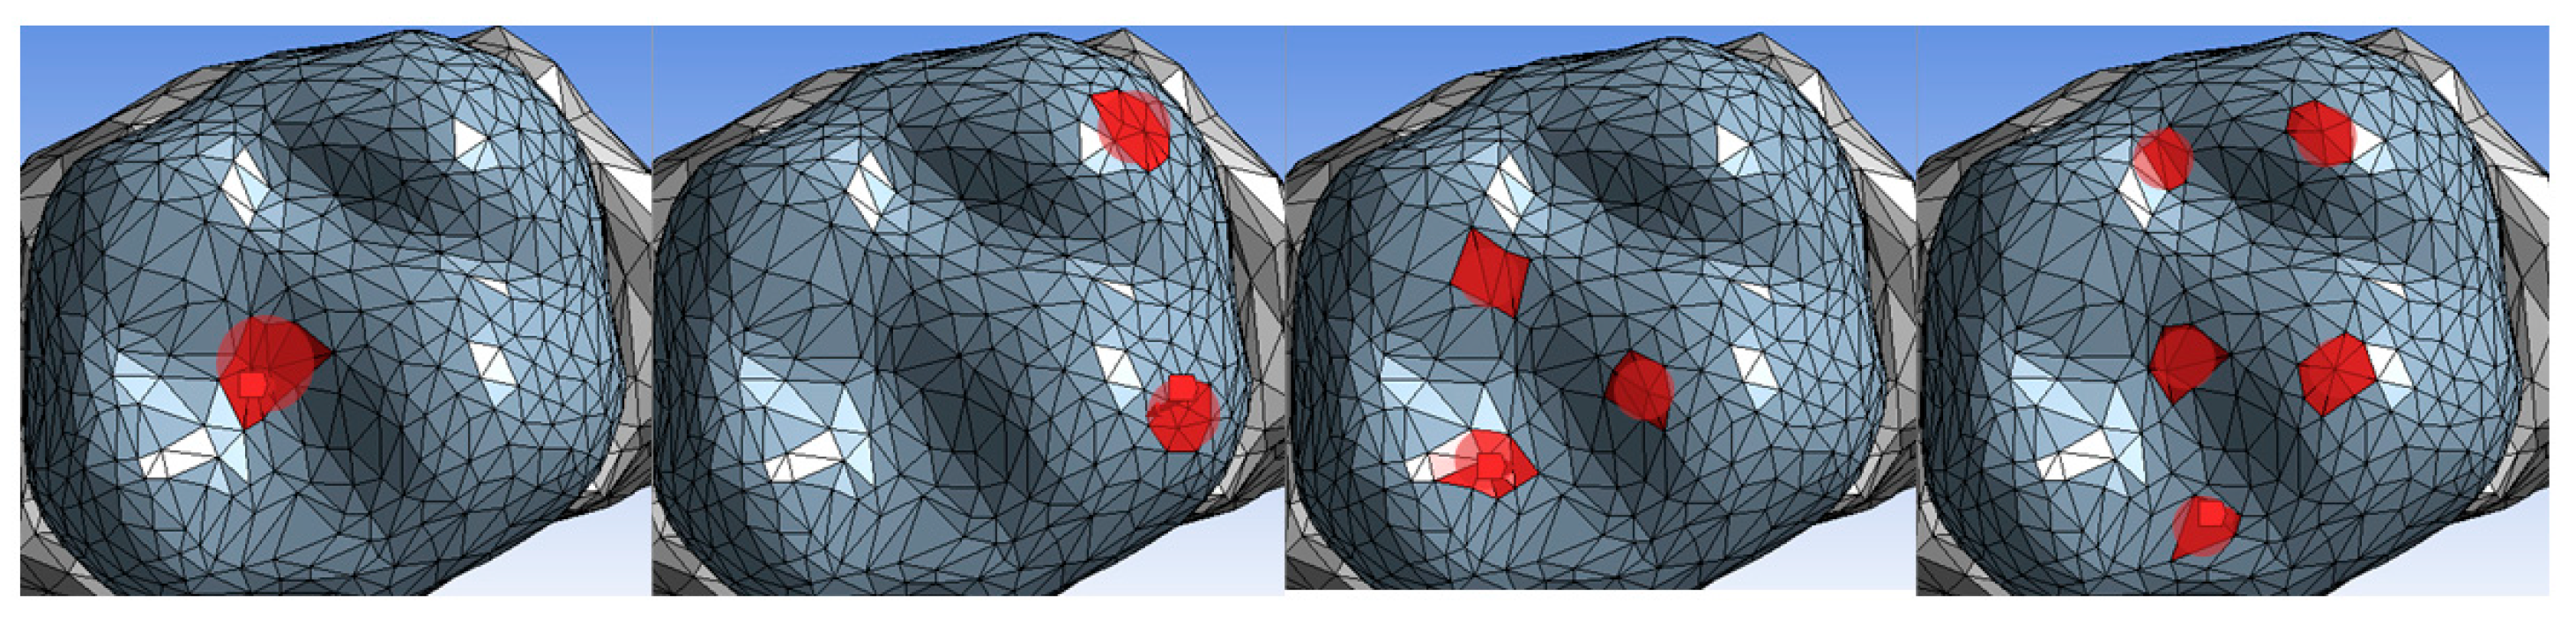

3.2. Stress-to-Strength Ratio (SSR)

3.3. Performance Under Bruxism Loads (800 N)

| Material Code | Flexural Resistance (MPa) | Von Mises Stress (MPa) F1, 250 N | Percentage Utilization (F1, %) | Von Mises Stress (MPa) F2, 225 N | Percentage Utilization (F2, %) | Von Mises Stress (MPa) F3, 400 N | Percentage Utilization (F3, %) | Von Mises Stress (MPa) F5, 800 N | Percentage Utilization (F5, %) |

|---|---|---|---|---|---|---|---|---|---|

| UF | 73 | 88.595 | 121.36 | 53.963 | 73.92 | 78.132 | 107.03 | 128.92 | 176.60 |

| LT | 113 | 87.568 | 77.49 | 54.392 | 48.14 | 80.671 | 71.39 | 122.79 | 108.66 |

| LC | 115 | 90.906 | 79.05 | 53.633 | 46.64 | 83.066 | 72.23 | 131.39 | 114.25 |

| PT | 119 | 91.296 | 76.71 | 53.353 | 44.83 | 83.682 | 70.23 | 132.21 | 111.10 |

| TC | 130 | 90.367 | 69.51 | 53.665 | 41.28 | 78.526 | 60.40 | 130.52 | 100.40 |